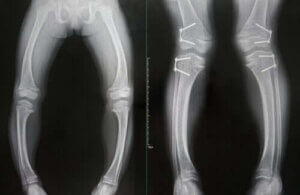

Sjukdomen kännetecknas av tillväxtfördröjning och bendeformiteter. Den är vanligast hos barn mellan sex månader och tre års ålder, eftersom det är det snabbaste tillväxtstadiet i en människas liv.

Hämmad tillväxt är det främsta symptomet på rakit. Sjukdomen orsakar deformationer i benen, som mjuknar. Det kan leda till böjda, krumma ben hos de drabbade. Det kan också orsaka slitage i ändarna på vissa ben.

Diagnosen baseras på en kombination av förändrade analytiska och radiografiska observationer och närvaron av de typiska kliniska symptomen som vi gick igenom ovan.